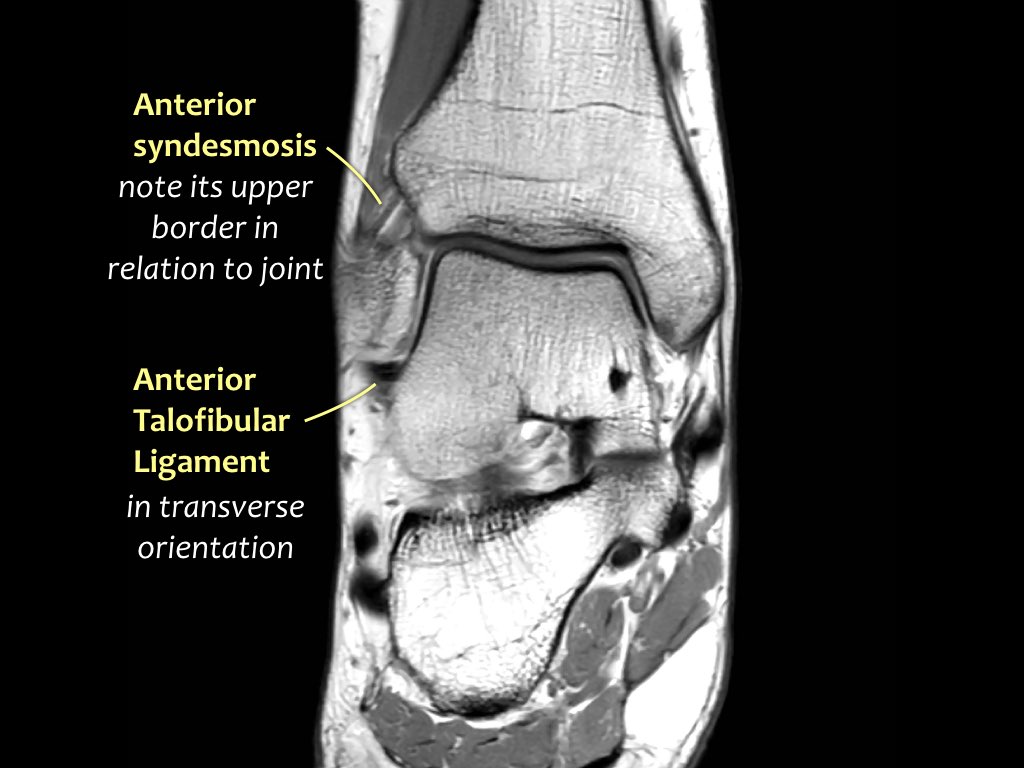

MRI Of The Foot | Radiology Key

mri foot radiology

Ankle And Foot | Radiology Key

foot ankle radiology fig radiologykey

mri radiology

Ankle And Foot | Radiology Key

foot ankle axial radiology medial sole lateral radiologykey